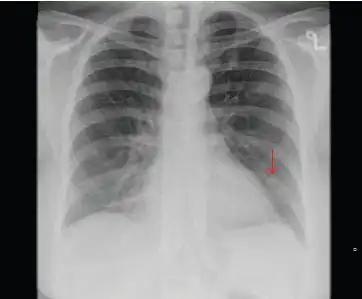

图1:胸片示一个1.3厘米的结节,箭头所示).